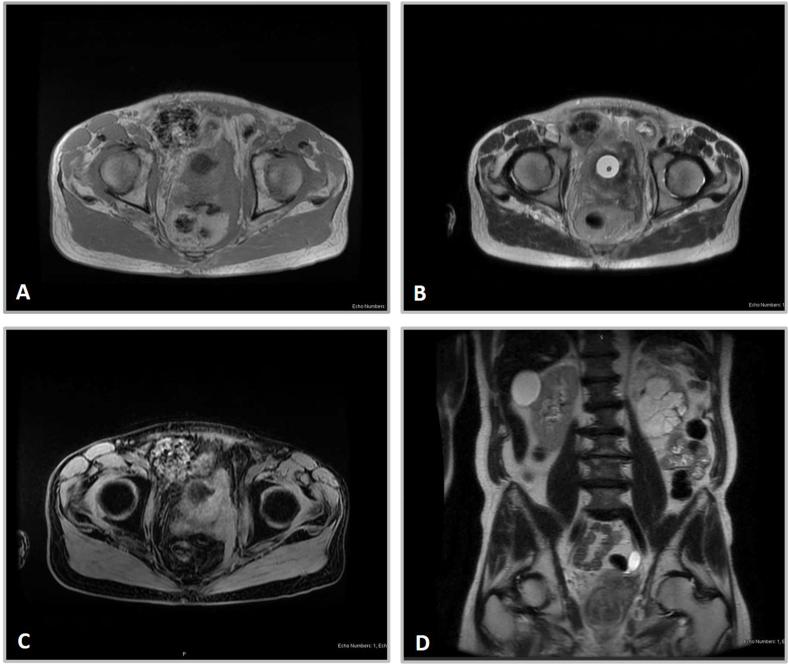

We present a case of muscle-invasive bladder cancer arising in a man who had previously been diagnosed with prostate cancer. His prostate cancer diagnosis and subsequent treatment with external beam radiation therapy occurred over 20 years prior to being diagnosed with bladder cancer. Biopsies of the bladder mass revealed a high-grade urothelial carcinoma with prostatic invasion and MRI showed significant concern for invasion into the pelvic floor. Metastatic lesions on his right rib and left clavicle were discovered on bone scan.

我们报告一例肌肉浸润性膀胱癌病例,患者此前被诊断患有前列腺癌。他的前列腺癌诊断及随后的外照射放疗发生在被诊断出膀胱癌的20多年前。膀胱肿块活检显示为高级别尿路上皮癌伴前列腺侵犯,MRI显示高度怀疑侵犯至盆底。骨扫描发现其右侧肋骨和左侧锁骨有转移灶。